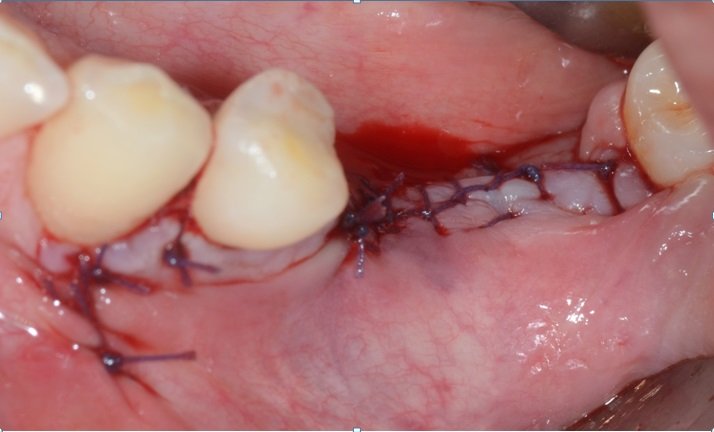

Sutura feita com vicryl 4-0 e raio-x pós-cirúrgico.